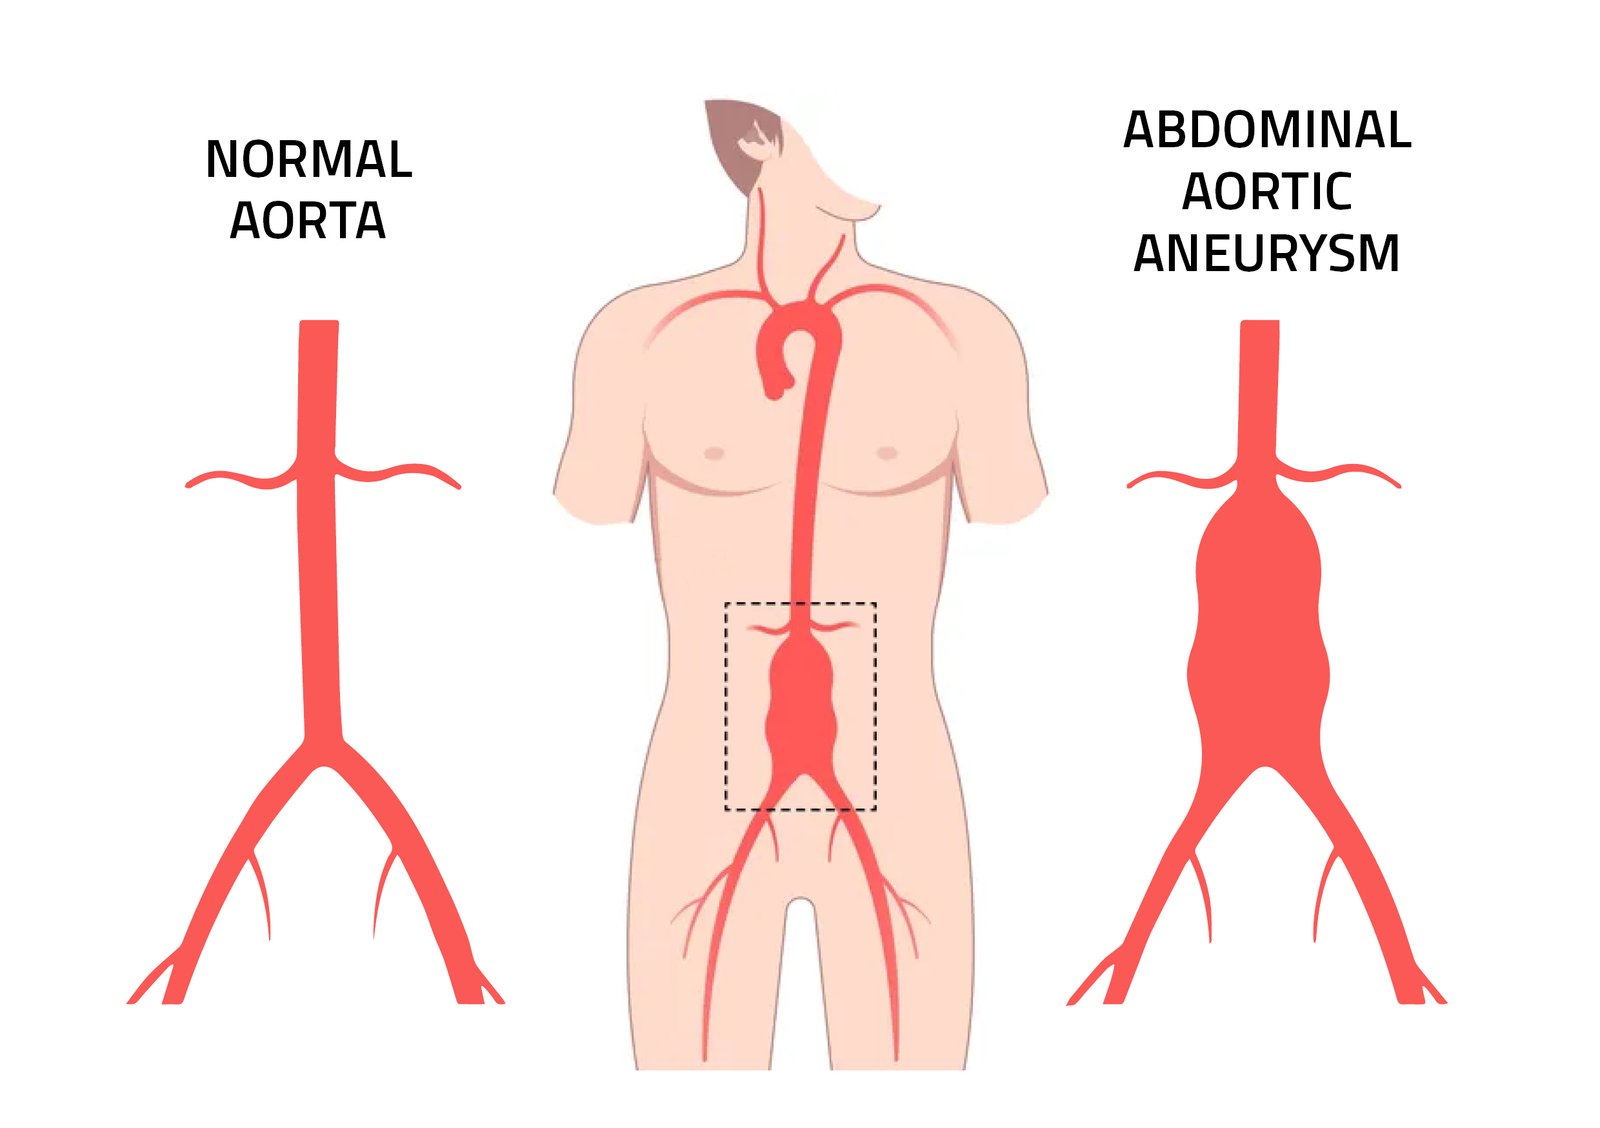

What is an Abdominal Aortic Aneurysm?

An abdominal aortic aneurysm (AAA) is a bulging or weakening of the aorta, the main artery that carries blood from the heart to the rest of the body. As this section of the aorta weakens, it can enlarge and form an aneurysm, which poses a serious risk. If the aneurysm ruptures, it may lead to life-threatening internal bleeding.

Many patients with an AAA may not experience any symptoms until it becomes critical. However, some might feel abdominal or back pain or notice a pulsing sensation near their navel. Regular check-ups and screenings, especially for those at higher risk, such as older adults or individuals with a family history of heart disease, are vital for early detection.

Determining whether you are a candidate for EVAR involves several important factors. Generally, EVAR is recommended for patients with AAAs that are larger than 5 cm in diameter or those that are growing rapidly. The decision is also influenced by the shape and health of your blood vessels.